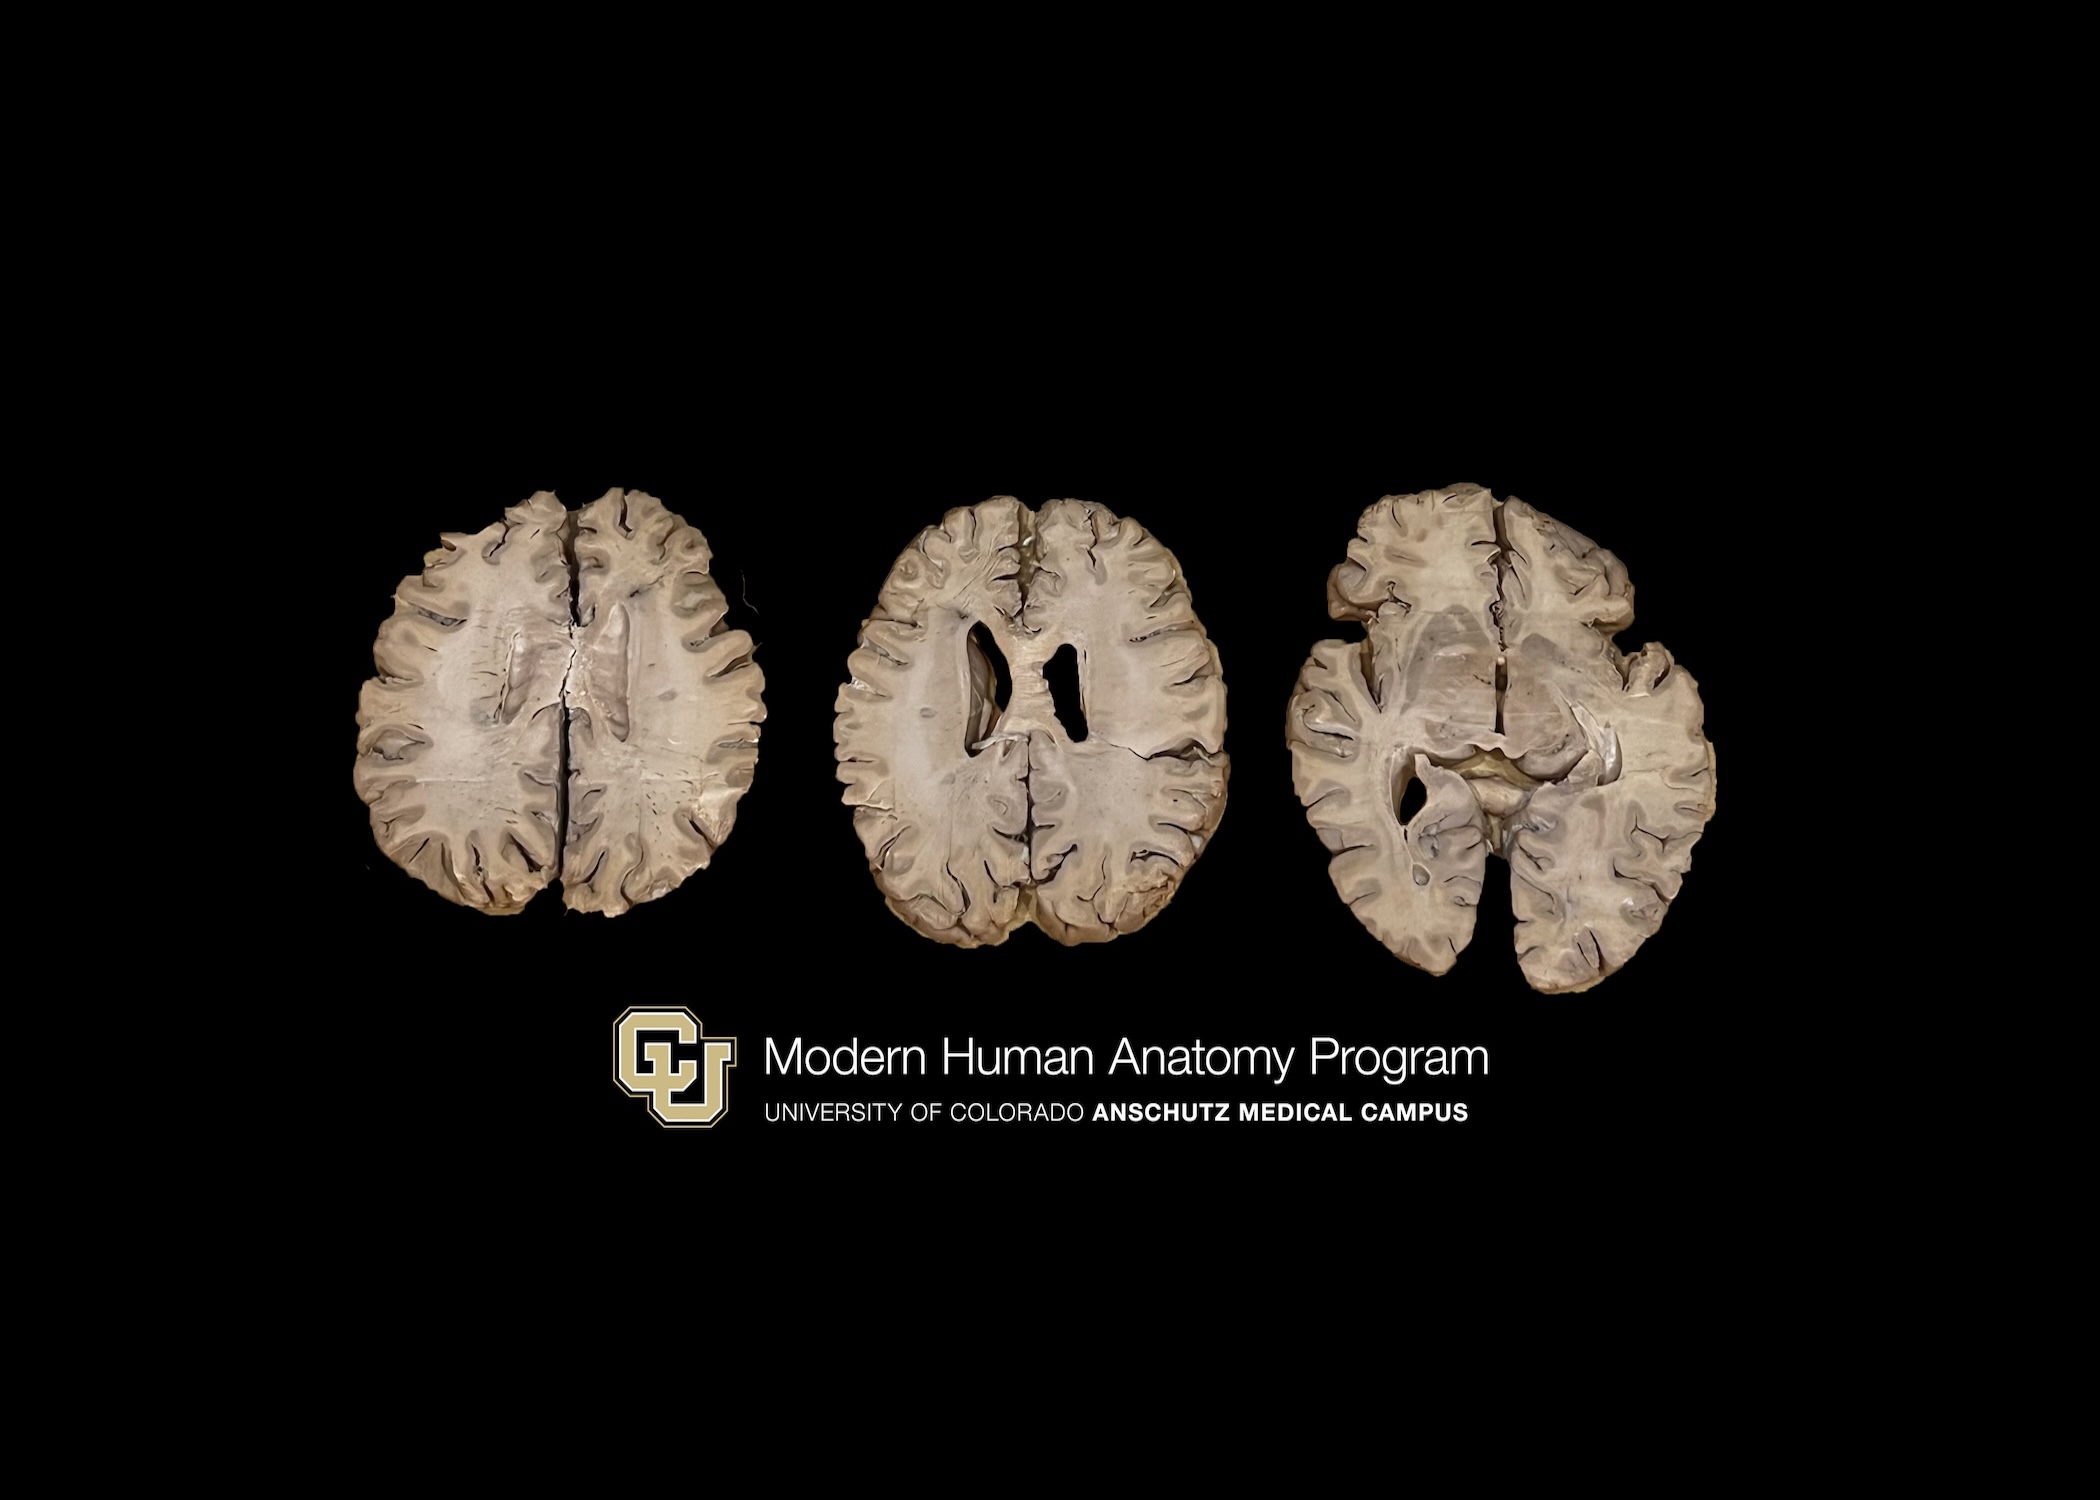

Axial slices of brain with Multiple sclerosis (3 pieces)

Axial Slices of Brain with Multiple Sclerosis

(3 pieces)